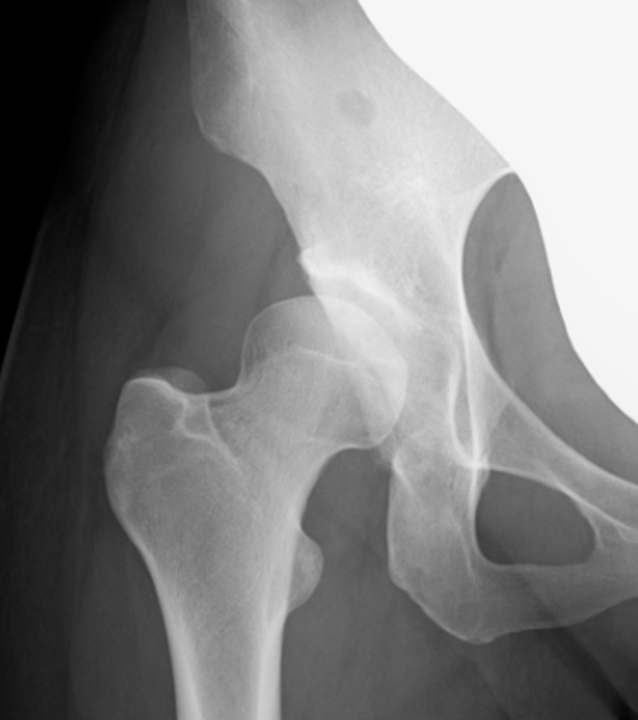

【術前】

人工股関節置換術術前